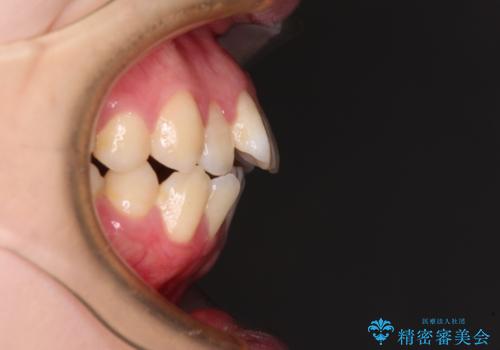

強い舌の突出癖により、上下前歯が前方に飛び出しており、特に上顎前歯は下顎よりも更に前方に位置している状態でした。

上顎前歯をしっかりと後方に移動させるため、口蓋側にアンカースクリューと補助装置を併用し、上下左右の第一小臼歯4本を抜歯し、ワイヤー装置にて矯正治療を行うこととしました。

口元の突出感が改善されてことで、下唇に引っかかっていた上顎前歯も気にならなくなりました。